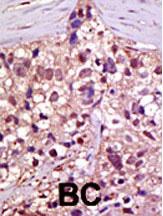

Formalin-fixed and paraffin-embedded human cancer tissue reacted with the primary antibody, which was peroxidase-conjugated to the secondary antibody, followed by AEC staining. This data demonstrates the use of this antibody for immunohistochemistry; clinical relevance has not been evaluated. BC = breast carcinoma; HC = hepatocarcinoma. |